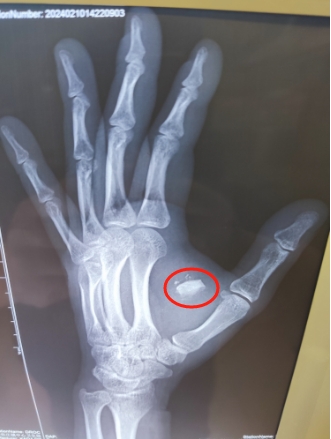

在betway在线登陆,医生对患者进行了全面的评估,包括详细的病史询问和体格检查。随后,医生安排了X光摄片,结果发现有异物残留在伤口附近。这一发现立即引起了医生的高度警觉,因为异物如果不及时清除,可能会导致感染甚至更严重的后果。

为了确保患者的安全,betway在线登陆的医生决定进行手术探查。在严格的无菌条件下,医生小心翼翼地打开了原来的缝合部位,仔细寻找并最终成功取出了异物。手术后,患者的伤口得到了妥善处理,并在医生的建议下,接受了必要的抗生素治疗以预防感染。